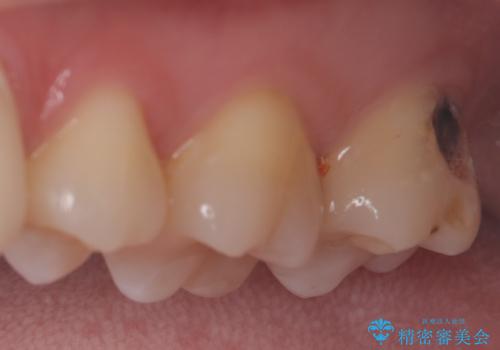

最新の症例

Latest cases